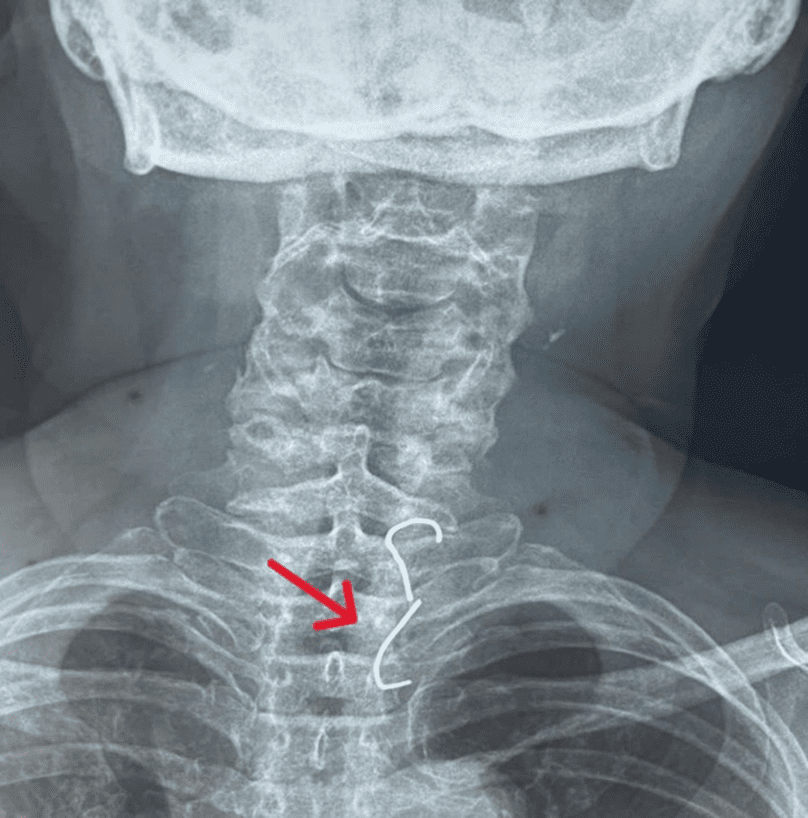

Bệnh nhân Kim Thị K. (61 tuổi) vào cấp cứu trong tình trạng không ăn uống được, nặng ngực, khó thở, mệt mỏi. Theo thông tin bệnh nhân cung cấp thì trước nhập viện 1 ngày, bệnh nhân nuốt phải răng giả hàm trên có 3 cây răng giả và móc kim loại. Sau đó, bác sĩ Khoa Tai Mũi Họng cho chụp X-quang cổ ngực thấy có dị vật cản quang bất thường, có hình móc câu ở 2 đầu, vị trí nằm ngang đốt sống ngực T1 - T2.

Hình chụp X-quang dị vật trong thực quản bệnh nhân